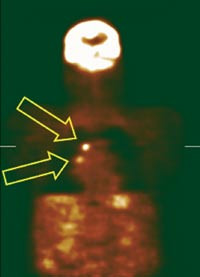

En metaanalyse, som omfatter 16 studier med til sammen 894 pasienter, viste at etter PET-undersøkelse ble stadieinndeling på grunnlag av lymfeknuter i mediastinum (fig 1) endret hos 16,7 % (8). En lavere prosentvis andel ble nedgradert til stadiene I eller II, og derfor operable (14 %), enn de som ble oppgradert til stadiene III eller IV, som ikke-operable (23 %). Ho og medarbeidere rapporterer videre at PET-undersøkelse var meget robust i differensiering mellom stadiene II og III og at PET-undersøkelsen hadde en meget høy negativ prediktiv verdi. Dersom PET-undersøkelse ikke viser lymfeknutemetastaser i mediastinum eller perifere metastaser, kan pasienten opereres. Spesifisiteten ble beregnet til 92,2 %, men det forekommer noen falskt positive undersøkelser. Forfatterene anbefaler derfor at en positiv undersøkelse etterfølges av kirurgisk stadieinndeling for å sikre at ingen pasienter mister muligheten til potensielt kurativ behandling (8).